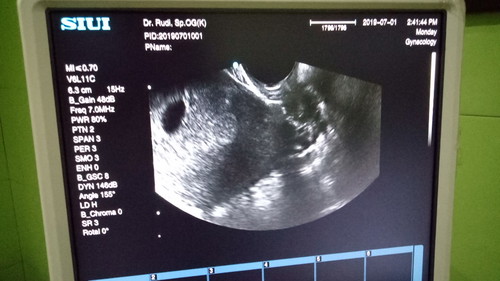

Maaf bun, mau tanya. Saya hpht 28 April 2019. Stlh dnyatakan postf tgl 29 Mei saya lgsng usg dan baru penebalan rahim saya dresepkan pnguat dan vtmin karena sebelumnya saya pernah abortus spontan diusia 5w tgl 6 maret 2019. Dr tgl 25 saya flek coklat smpai hari ini sdh 8hr msh flek coklat. Kmren tgl 1 saya usg lagi melalui transv, kata dokter diusia kndungan segini shrusnya sdh ada detak jantungnya, 80% kemngkinan BO dan cm ada 20% kmngkinan janin berkmbang. Mnrt bunda gmn? Sdngkan di usg saya jg g liat brp usian khmilan saya, dsuruh balik 2mnggu lagi untuk periksa. Ada gak bunda yg divonis bo, tp trnyata bayi bisa berkembang?